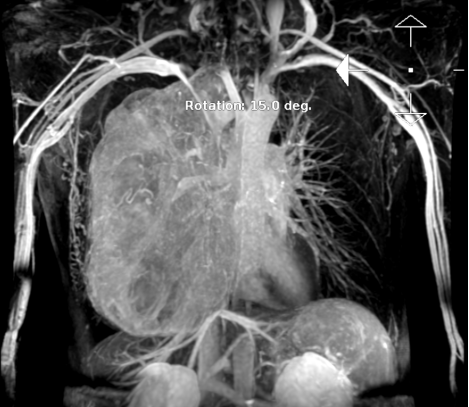

血管造影图像

经跨院区会诊后,胸外科陈龙奇教授团队收治患者,进一步完善相关检查,仔细评估手术风险并进行全科室讨论。患者肿瘤体积大、范围广,滋养血管丰富,侵犯右侧支气管;同时,肿瘤上至右侧胸顶,手术视野狭窄,操作受限,故应十分谨慎,避免伤及邻近血管和神经;此外,患者因右侧肺80%被肿瘤压迫不张存在重度混合性通气功能障碍,肺功能重度受损,上腔静脉以及胸椎椎体同样受到压迫,术中稍有不慎就会损伤血管和神经,甚至导致大出血。住院期间,患者通过常规检查膀胱发现新生物(术后病理为:乳头状尿路上皮癌)。这些都为手术增添了难度,也为手术技术处理提出了更高要求。